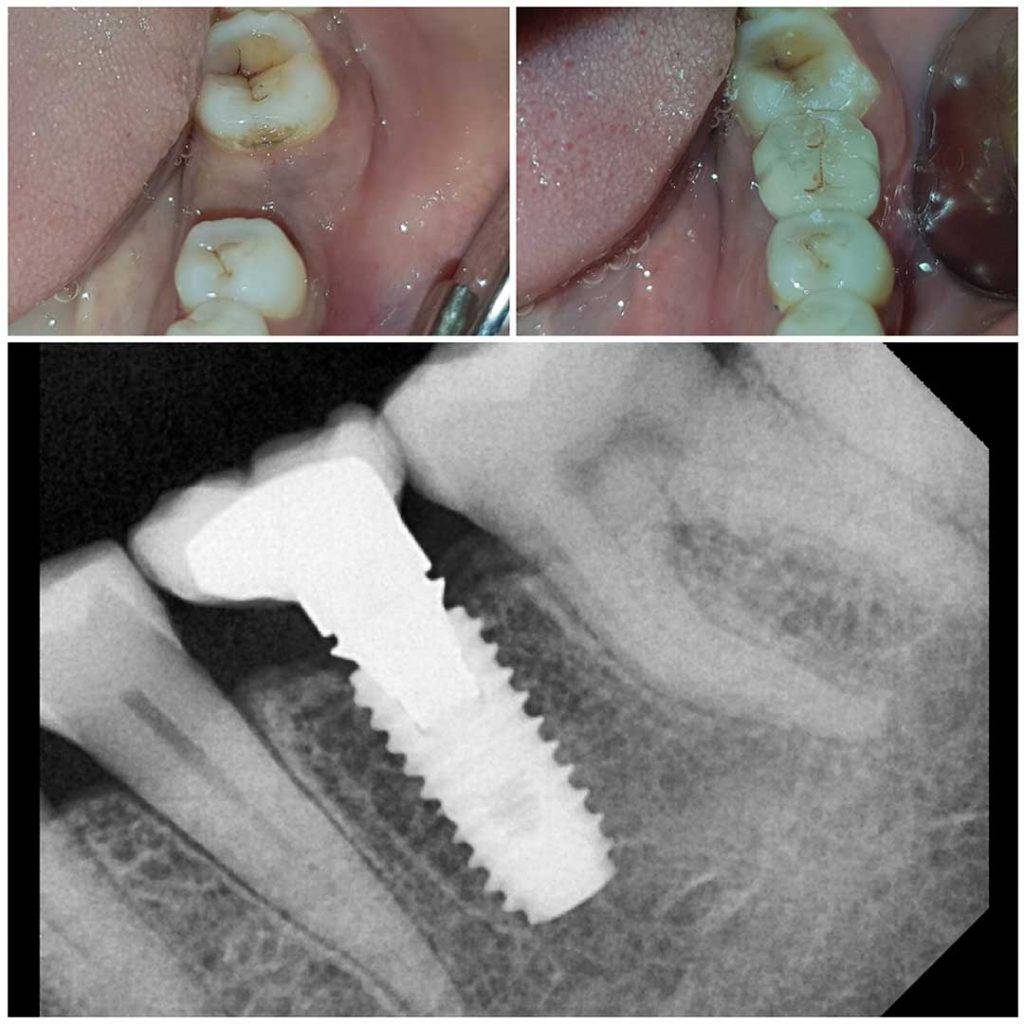

Treatment Gallery

At The Dental Tree & Facial Cosmetic Centre, the centre of our universe is our patients. Satisfaction of our patients has always been our top priority and always will be. This is the reason why we are the Best Dental Clinic in Indirapuram and why we do what we do.

Our Gallery